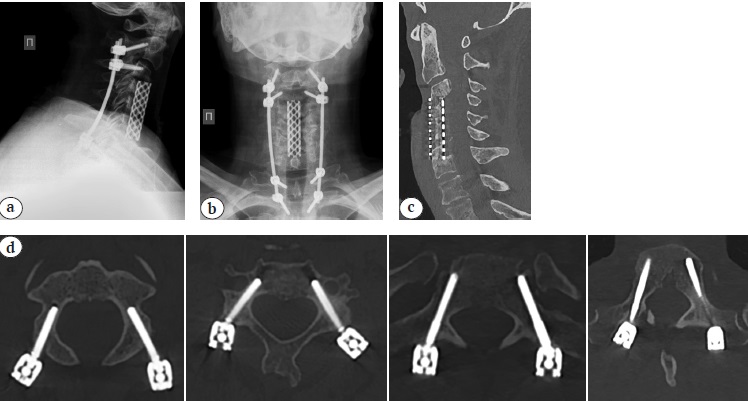

Radiological examination revealed an angular kyphotic deformity of the cervical spine of 48° according to Cobb, cSVA 12 mm, T1S 30° (Fig. 4).

Fig. 4. X–ray (a), CT (b) and MRI (c) at the time of hospital admission: angular kyphosis 48° Cobb, destruction of C3–С5, myelopathy at C2–С3, no signs of active inflammatory process (abscesses)

X-rays of the cervical spine at the time of discharge from the hospital and CT scans 10 months after the surgery are presented in Figure 5.

Fig. 5 (a, b, c, d). Sagittal (a) and frontal (b) X–rays, sagittal CT (c) 10 months after surgery: posterior transpedicular screw fixation correct position, solid anterior fusion C3–C7 formation detected. (d) - Axial (d) CT: posterior transpedicular screw fication correct position, solid anterior fusion C3–C7 formation detected

Postoperative period was uneventful, wounds healed by primary intention. Drains were removed on the 2nd day, patient was verticalized in a cervical brace on the 3rd day after the surgery. The intensity of vertebrogenic pain syndrome 10 months later was 2 points according to VAS, radicular pain syndrome in the upper extremities subsided, ODI – 15%, NDI – 14%. The value of correction of kyphotic deformity of the cervical spine was 46° according to Cobb.